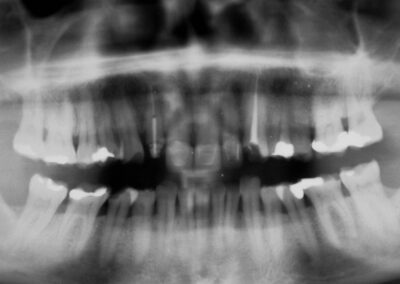

Präprothetisches OPT aus 1996, deutliche Zeichen für massiven Bruxismus, bei sehr resistentem Parodontium und/oder relativ weicher Zahnsubstanz (Klick!)